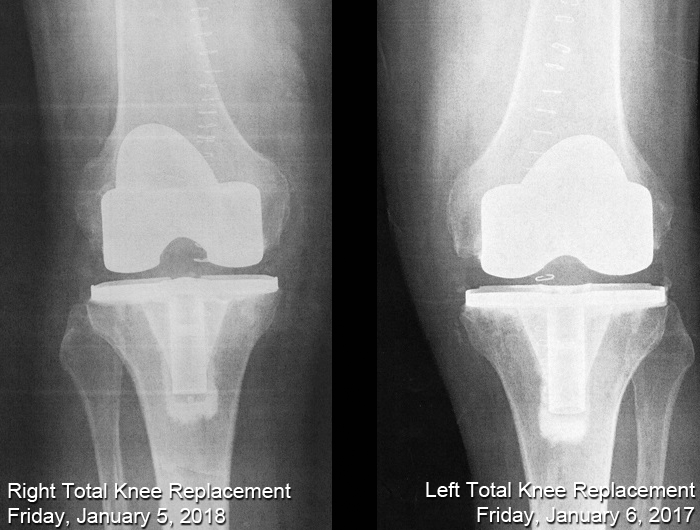

The first Friday in January will always be a significant day for me. On January 6, 2017, I had my left knee replaced. On January 5, 2018, I had my right knee replaced. Both knees had lost all their "bounce" over the last several years, but the left knee was more damaged than the right, so it went first.

The above are x-rays of the both knees post surgery. You can see the staples slightly, if you look closely. Notice how the legs are straightened in the process, thus relieving stress on the hips and back. Plus, I'm a little taller! Thank you Dr. Robie. You are an excellent surgeon!